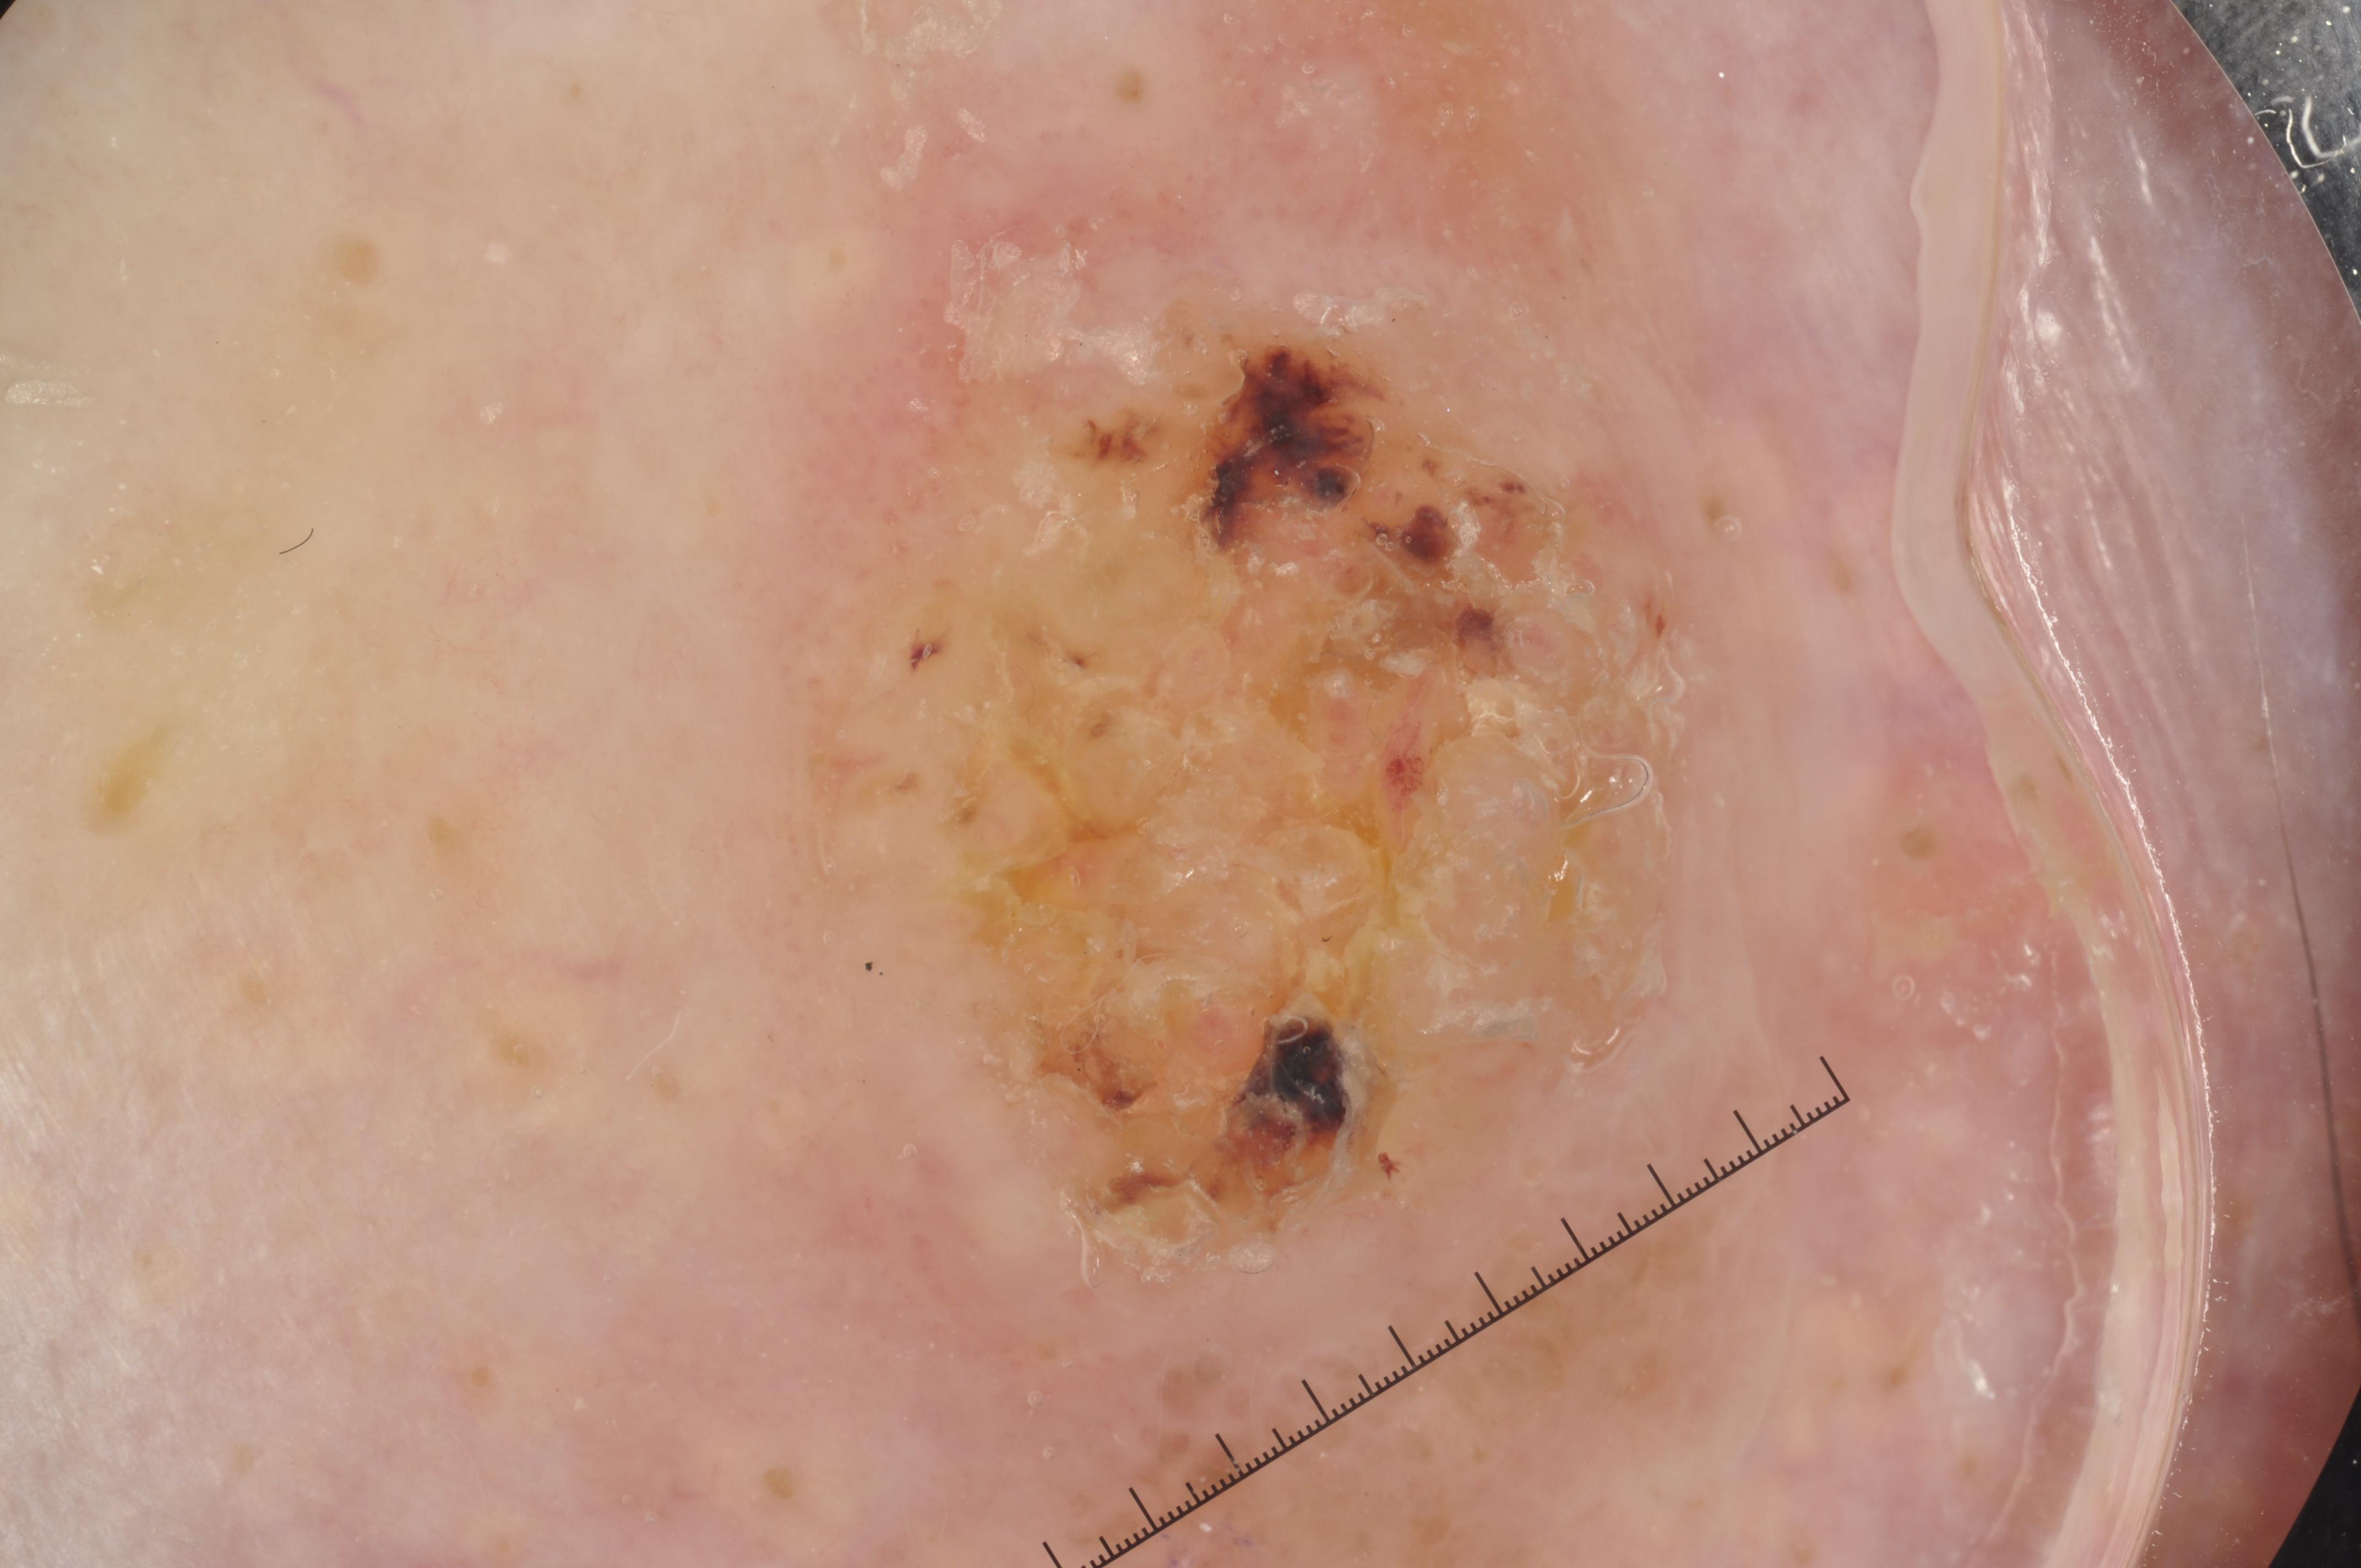

{

"age_approx": 85,

"anatom_site_general": "lower extremity",

"concomitant_biopsy": true,

"dermoscopic_type": "contact non-polarized",

"diagnosis_1": "Malignant",

"diagnosis_2": "Malignant epidermal proliferations",

"diagnosis_3": "Squamous cell carcinoma, NOS",

"diagnosis_confirm_type": "histopathology",

"image_type": "dermoscopic",

"lesion_id": "IL_0375857",

"melanocytic": false,

"sex": "male"

}